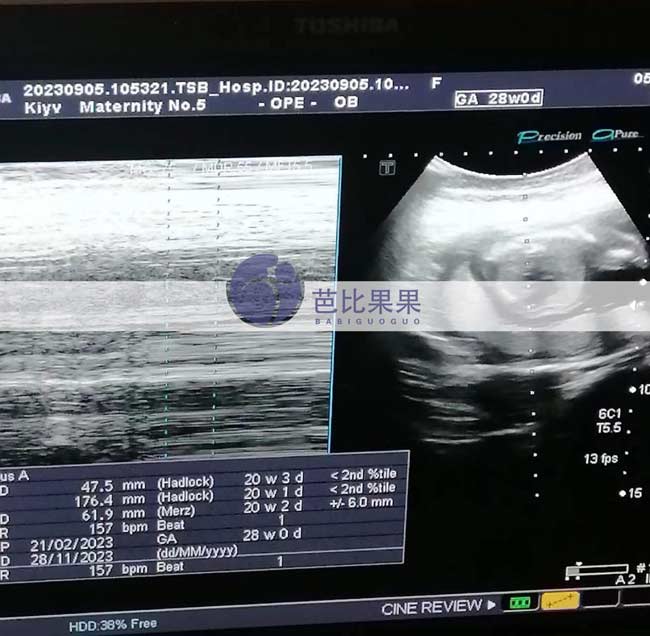

Y女士的乌克兰试管妈妈孕18+周,B超检查是个男娃

在格鲁吉亚试管助孕的Y女士的乌克兰试管妈妈孕18+周了,这次B超依旧面色红润、笑容满满。检查看到是个男娃了,一家人好开心。